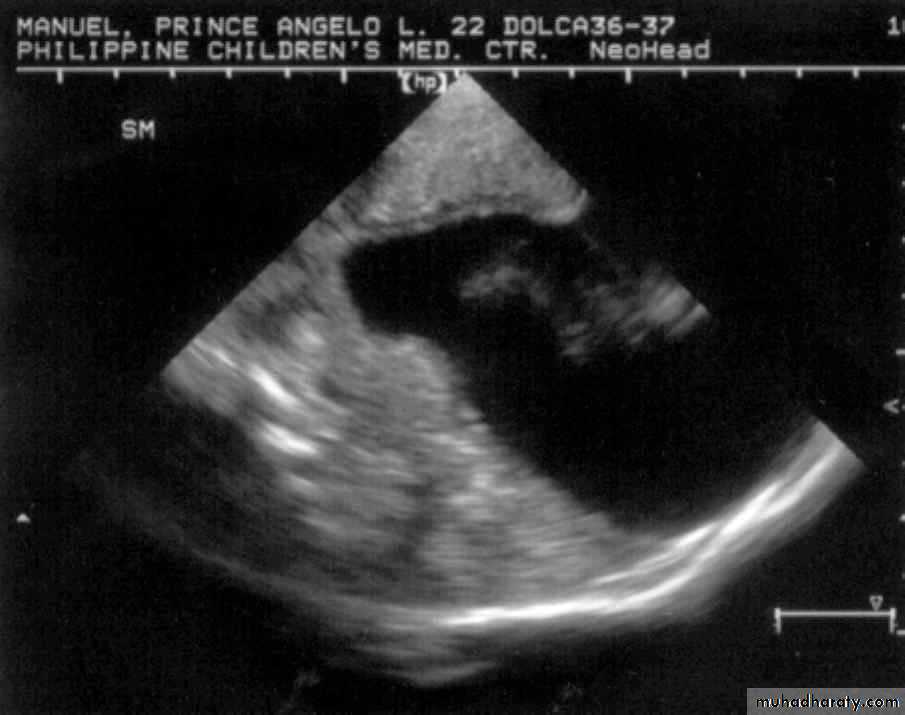

Neurulation Period11 mos old, male

Encephalocoele